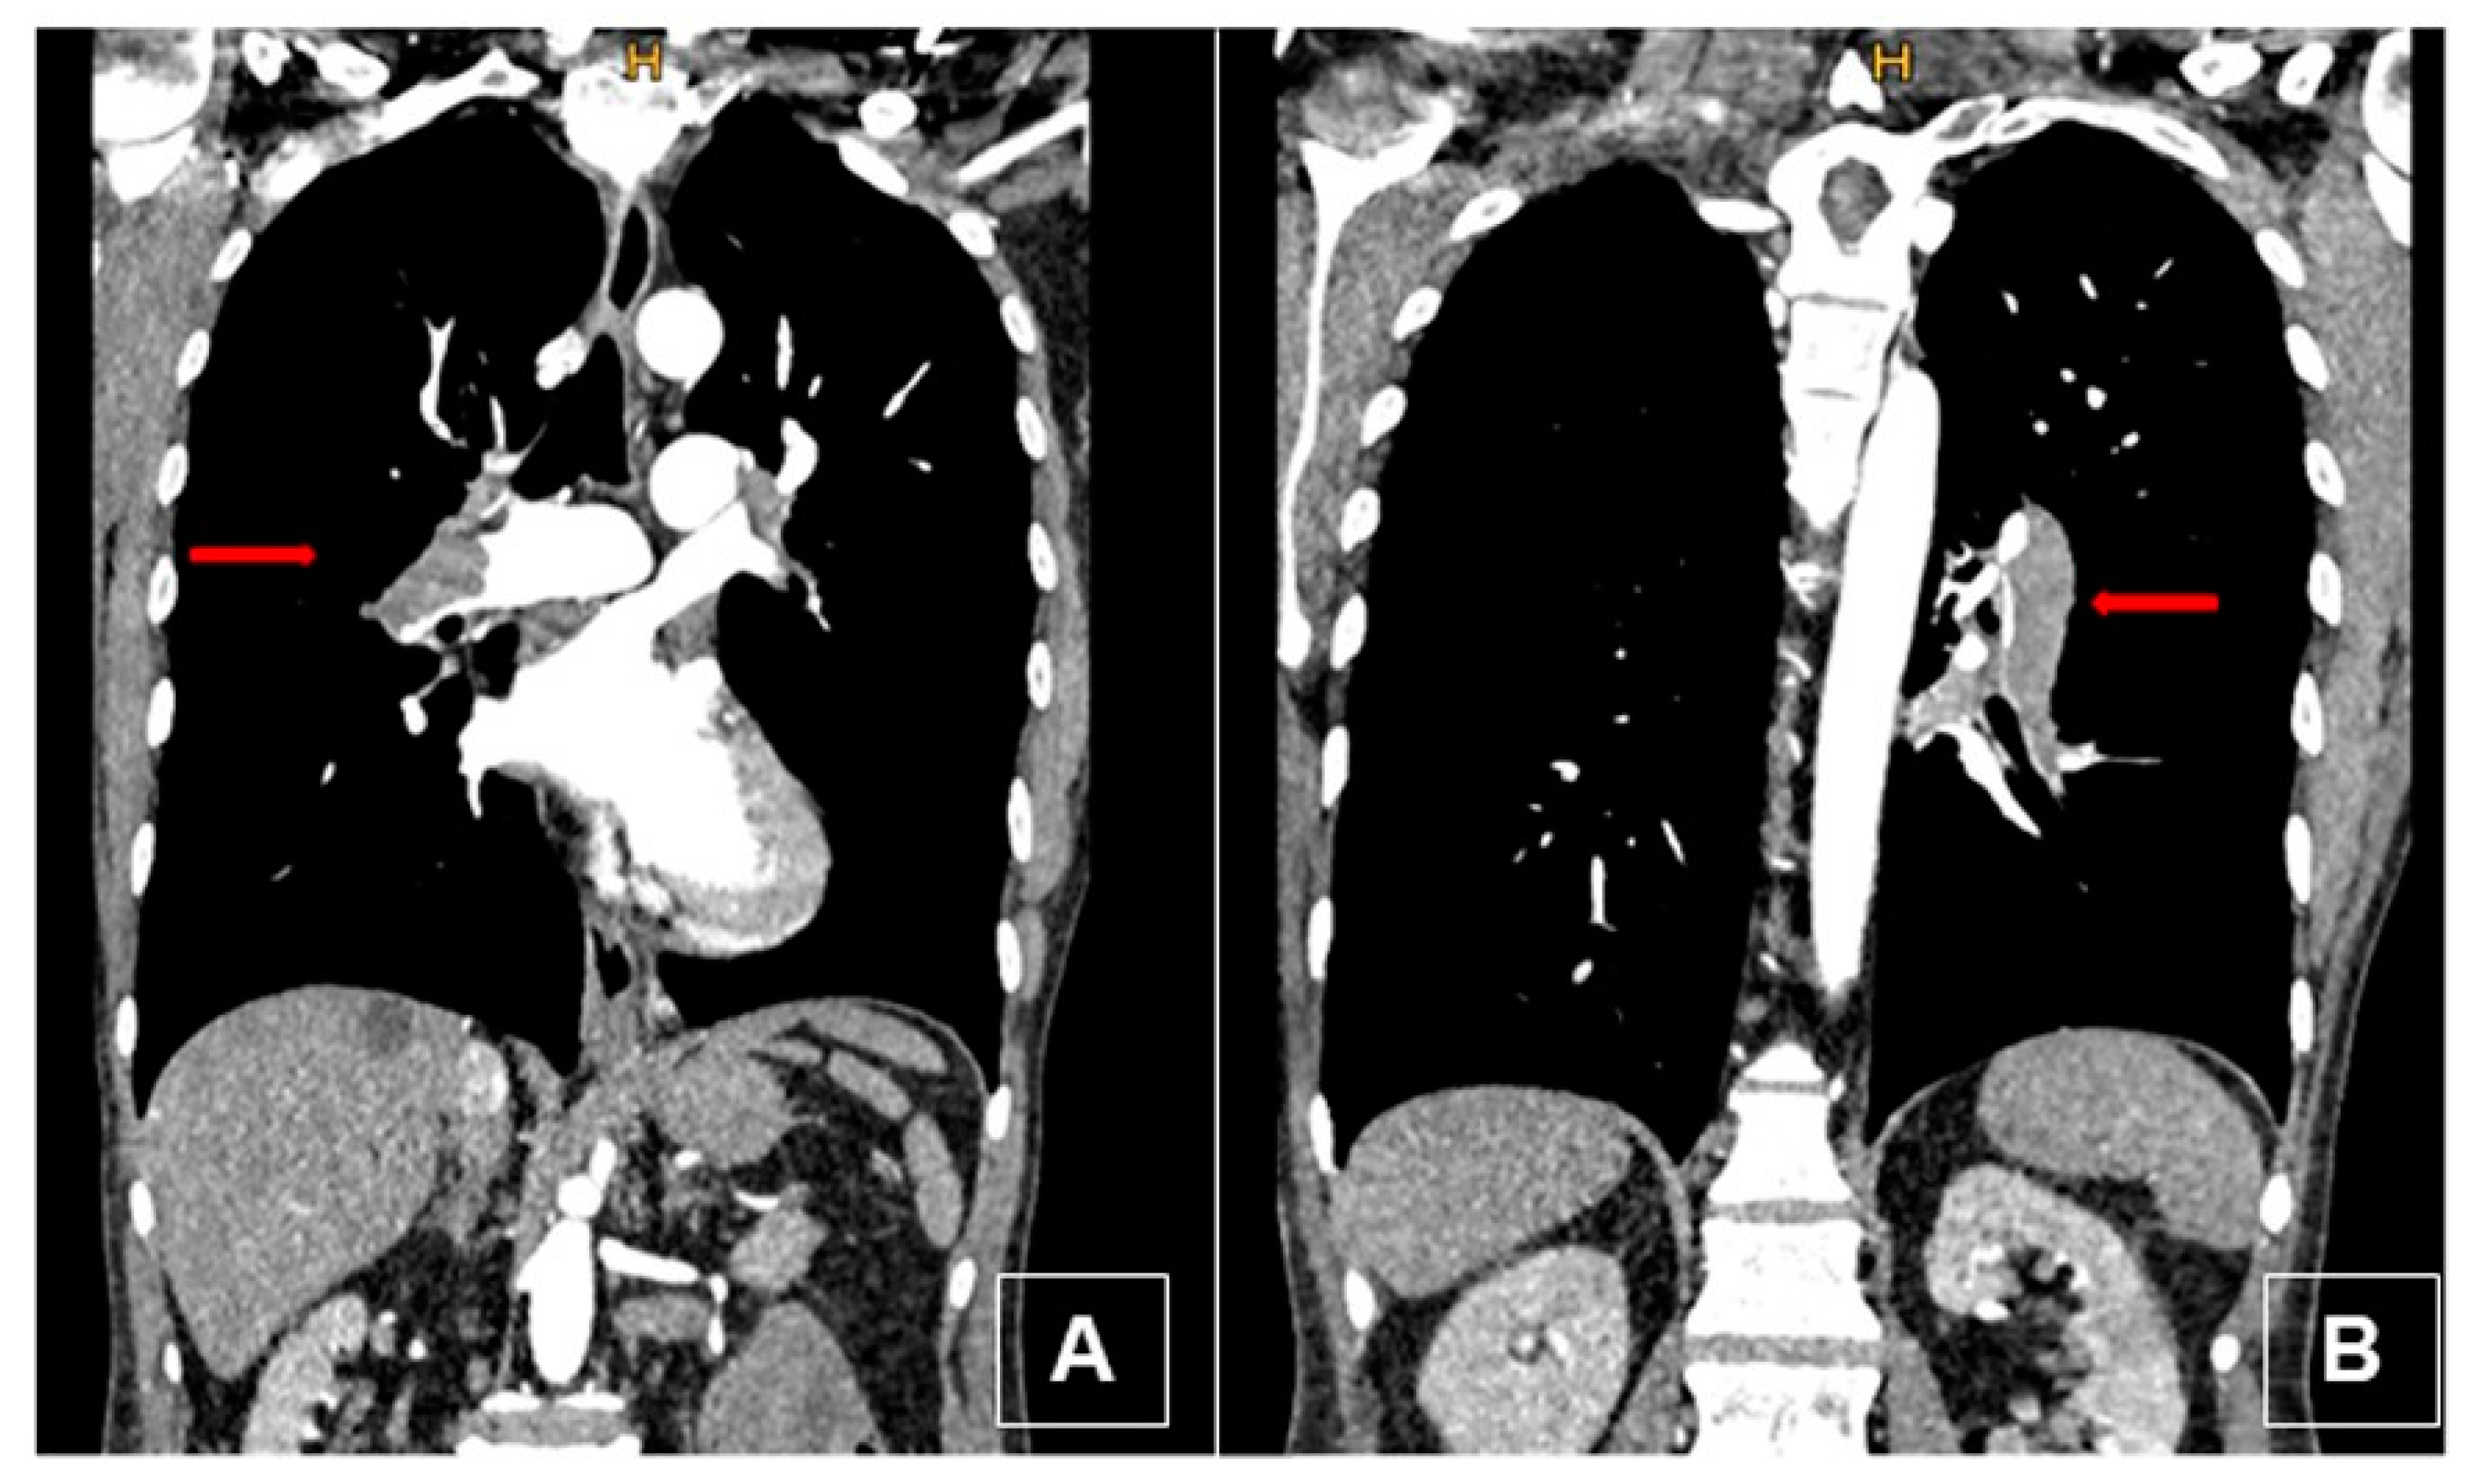

2.1. Case 1

2.2. Case 2

3.4. Computed Tomography Pulmonary Angiography (CTPA)